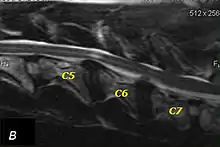

T2 weighted MRI in neutral (A) and linear traction (B) of a seven-year-old Doberman with a two-year history of cervical pain treated with NSAIDs and presented acutely tetraplegic: A C6-C7 and C5-C6 traction responsive myelopathy are evident on MRI. The spinal-cord hyperintensity seen at the C5-C6 is suggestive of chronic lesion and most likely responsible for the chronic history of cervical pain, while the C5-C6 lesion was most likely responsible for the acute tetraplegia.

Same dog (A) treated with double implant (B) three days after surgery: The dog became ambulatory three days after surgery. Four weeks after surgery, it had ataxia without conscious proprioceptive deficits, and three months after surgery, the dog was neurologically normal. The owner reported it had been two years since the dog was able to hold its neck in an elevated position.